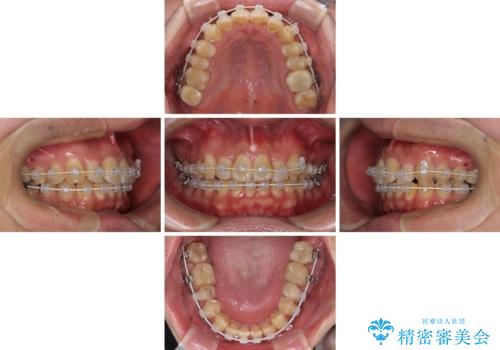

- 矯正装置

- 審美装置

- 治療期間

- 1年8ヶ月

上顎前歯が舌側に転位しており、なるべく早く楽に矯正したいとのことで、ワイヤー矯正を行うこととしました。